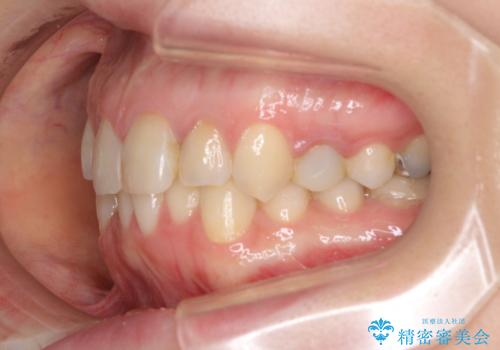

【モニター】前歯のデコボコと奥歯の虫歯 インビザライン治療と奥歯のセラミック治療

- 前歯のデコボコと奥歯の虫歯を気にして来院された患者様です。

主に下顎歯列全体の後方移動とIPR(歯と歯の間を削る)によってデコボコが解消するように設計し、インビザラインにより治療を行うこととしました。

矯正治療後半に下顎左右奥歯をセラミッククラウンにて補綴し、その後インビザラインによる歯列の仕上げを行うこととしました。

下顎前歯の叢生が速やかに改善されたため、1年3か月で治療を終えることができました。